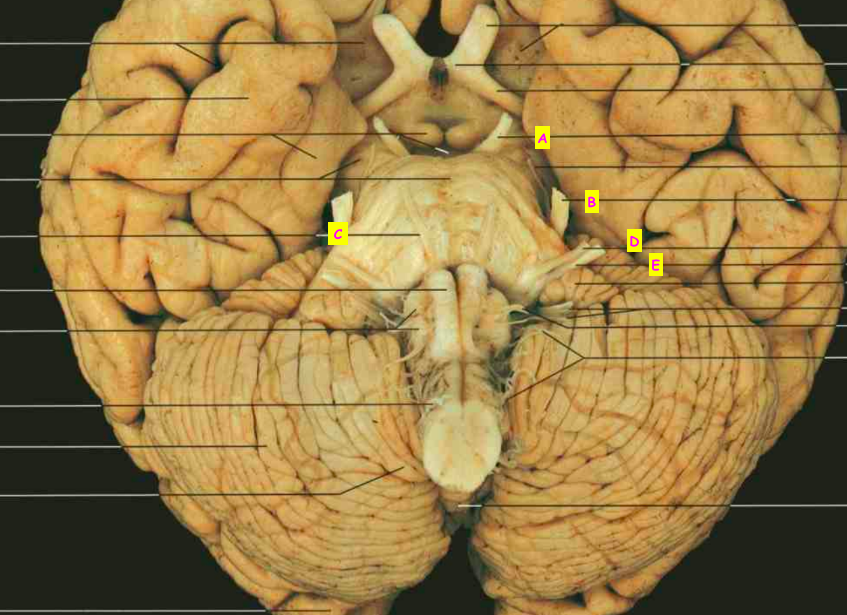

Which structures are the arrows pointing to? [5]

A

A: Oculomotor nerve (n. III)

B: Trigeminal nerve (n. V)

C: Abducent nerve (n. VI)

D: Facial nerve (n. VII)

E: Vestibulocochlear nerve (n. VIII)